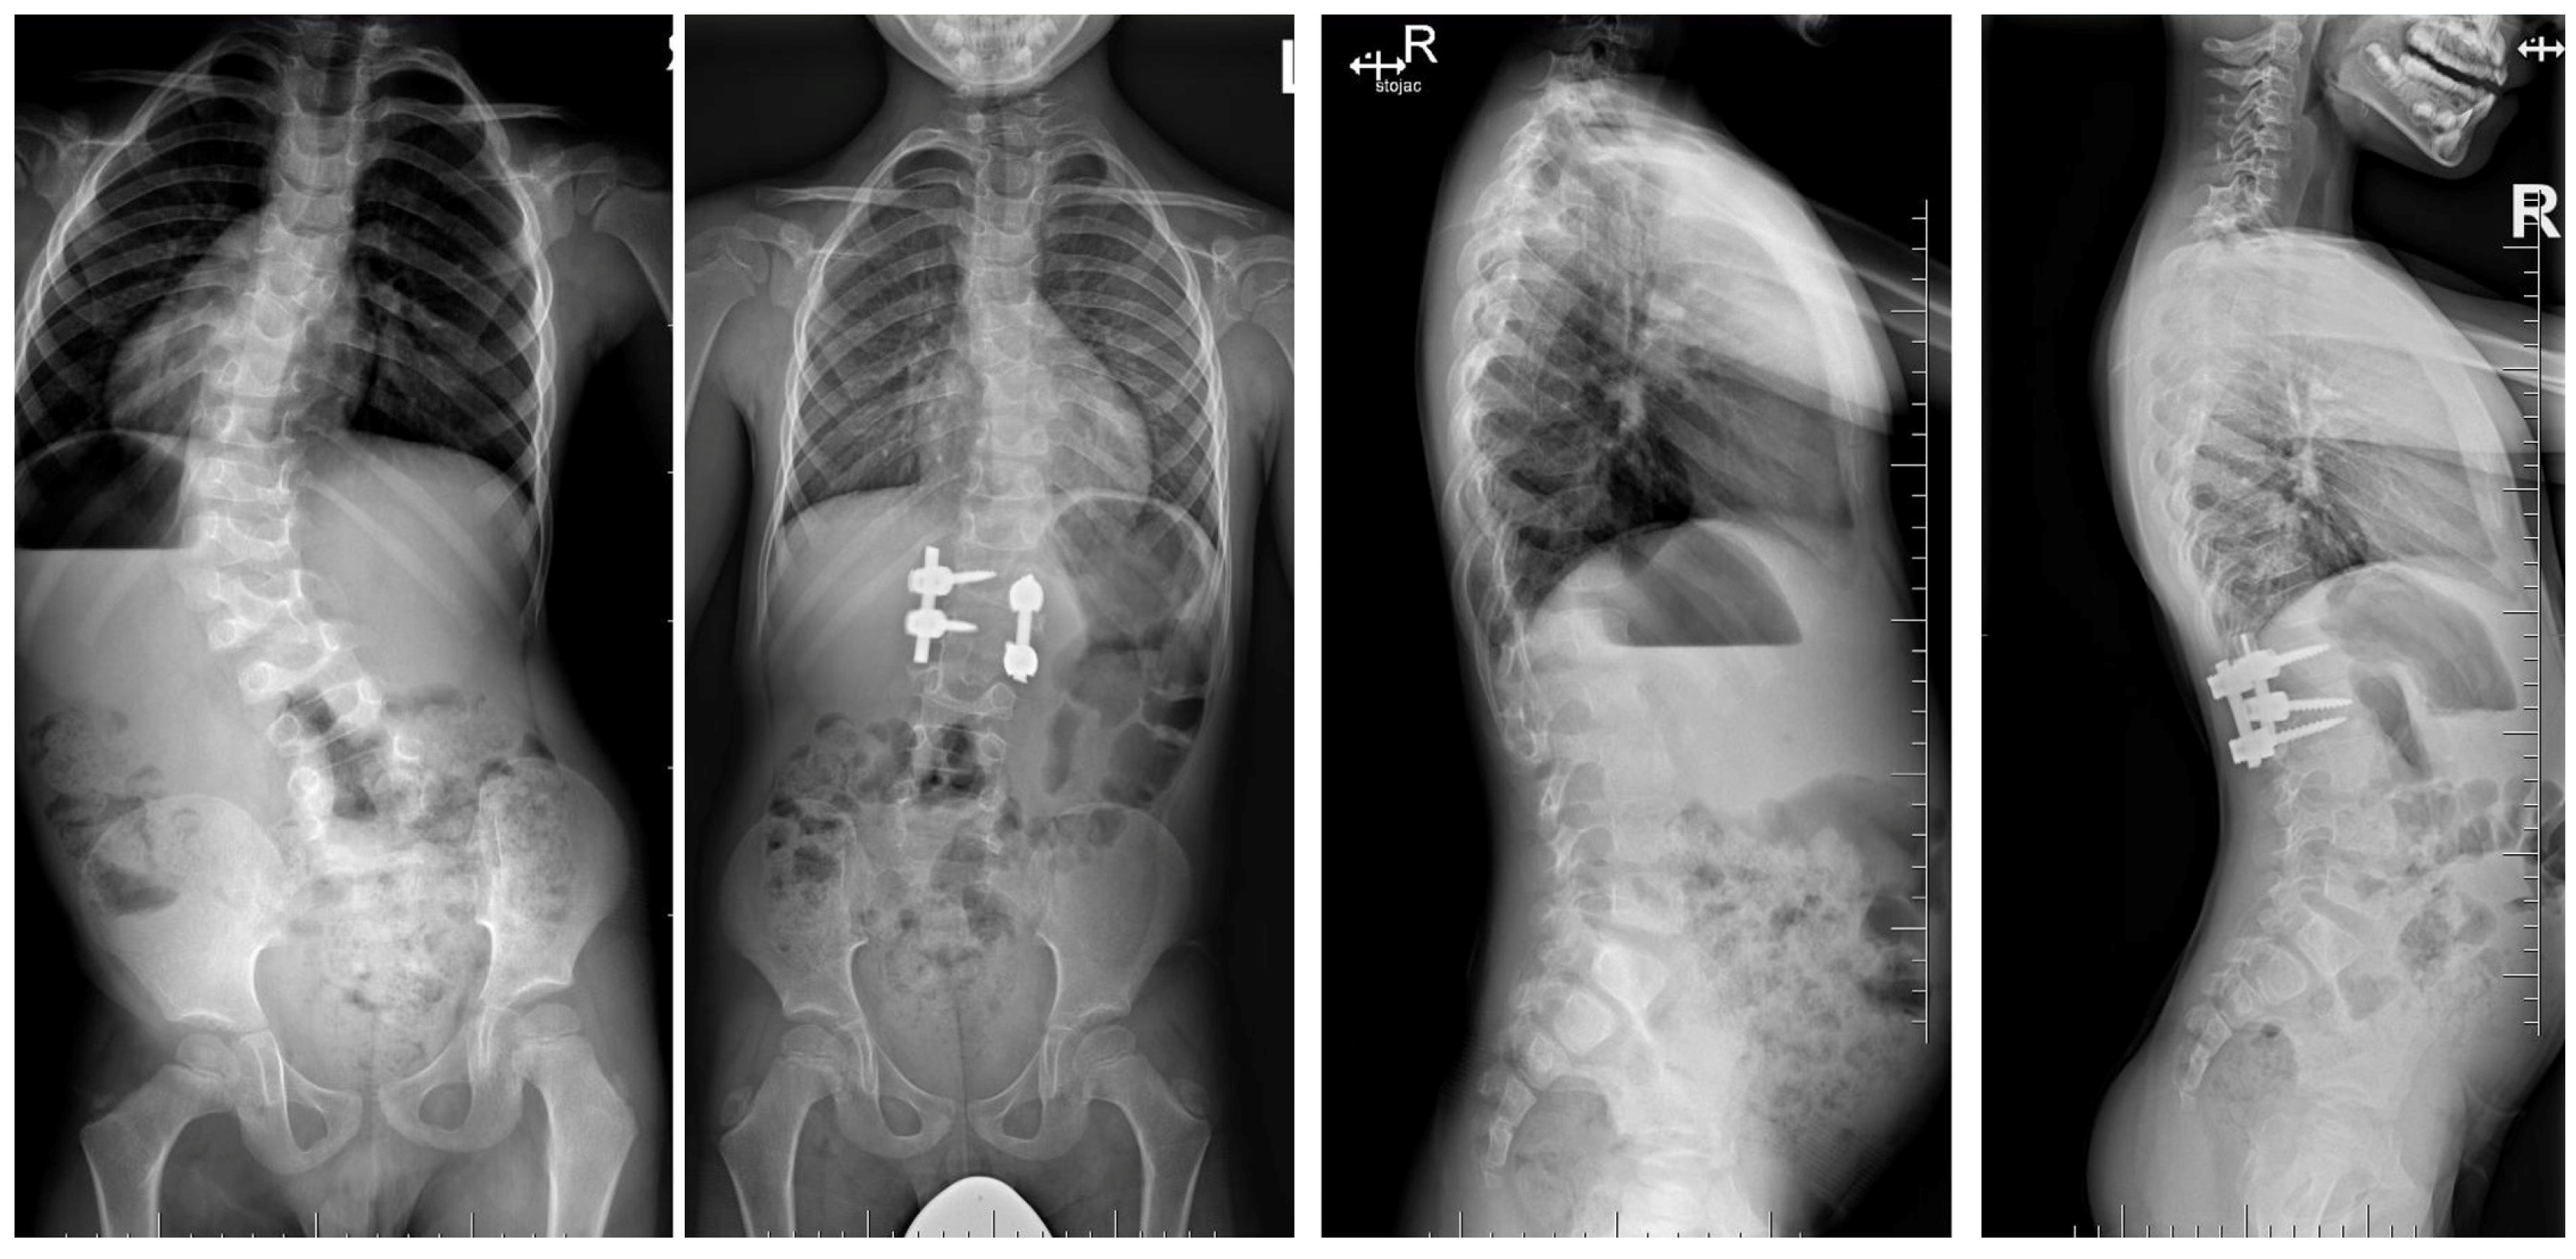

7.3. Surgical Techniques

7.3.4. Growing Rod Systems

8. Complications and Risk Management